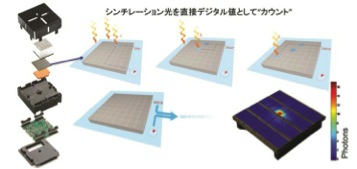

1.デジタルフォトンカウンティング技術

これまでシンチレーション光の検出は、検出器で捉えたアナログ信号のデジタル信号への変換(A/D変換)が必要だった。その際に発生するノイズや処理速度がシステムの課題とされていた。一方、デジタルフォトンカウンティング技術は1個のクリスタル4×4mm2あたり3200個のマイクロセルと呼ばれるデジタル半導体素子が無数のシンチレーション光を直接デジタル値としてカウントし、クリスタルのイベントを定義することで理想的なデジタル信号の検出と制御、数え落としの抑制と温度特性の改善までを可能としている。